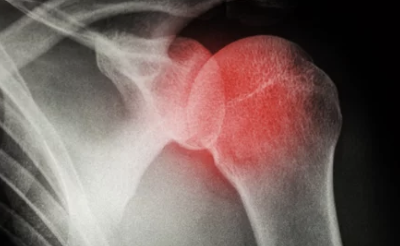

오십견(동결견, 유착성 관절낭염)은 어깨 관절이 굳고 움직이기 어려운 질환으로, 보통 50대 이후에 많이 발생한다고 해서 ‘오십견’이라는 이름이 붙었다. 어깨 관절을 감싸는 관절막이 염증으로 인해 두꺼워지고 유착되면서 통증과 운동 제한이 발생하는 것이 특징이다.

1. 오십견 주요 증상 & 원인